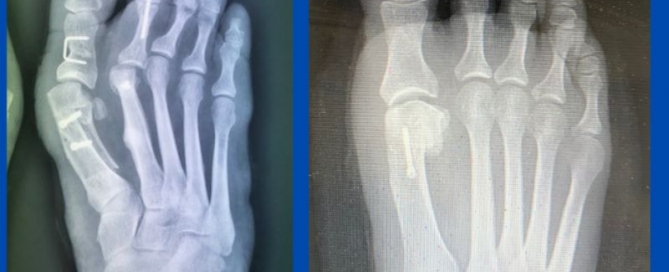

Dislocated 2nd MTPJ

Blog's main page This patient presented recently with a long-standing markedly painful left 2nd metatarsophalangeal joint (MTPJ). Conservative care has been unsuccessful and hence she was referred for a surgical [...]